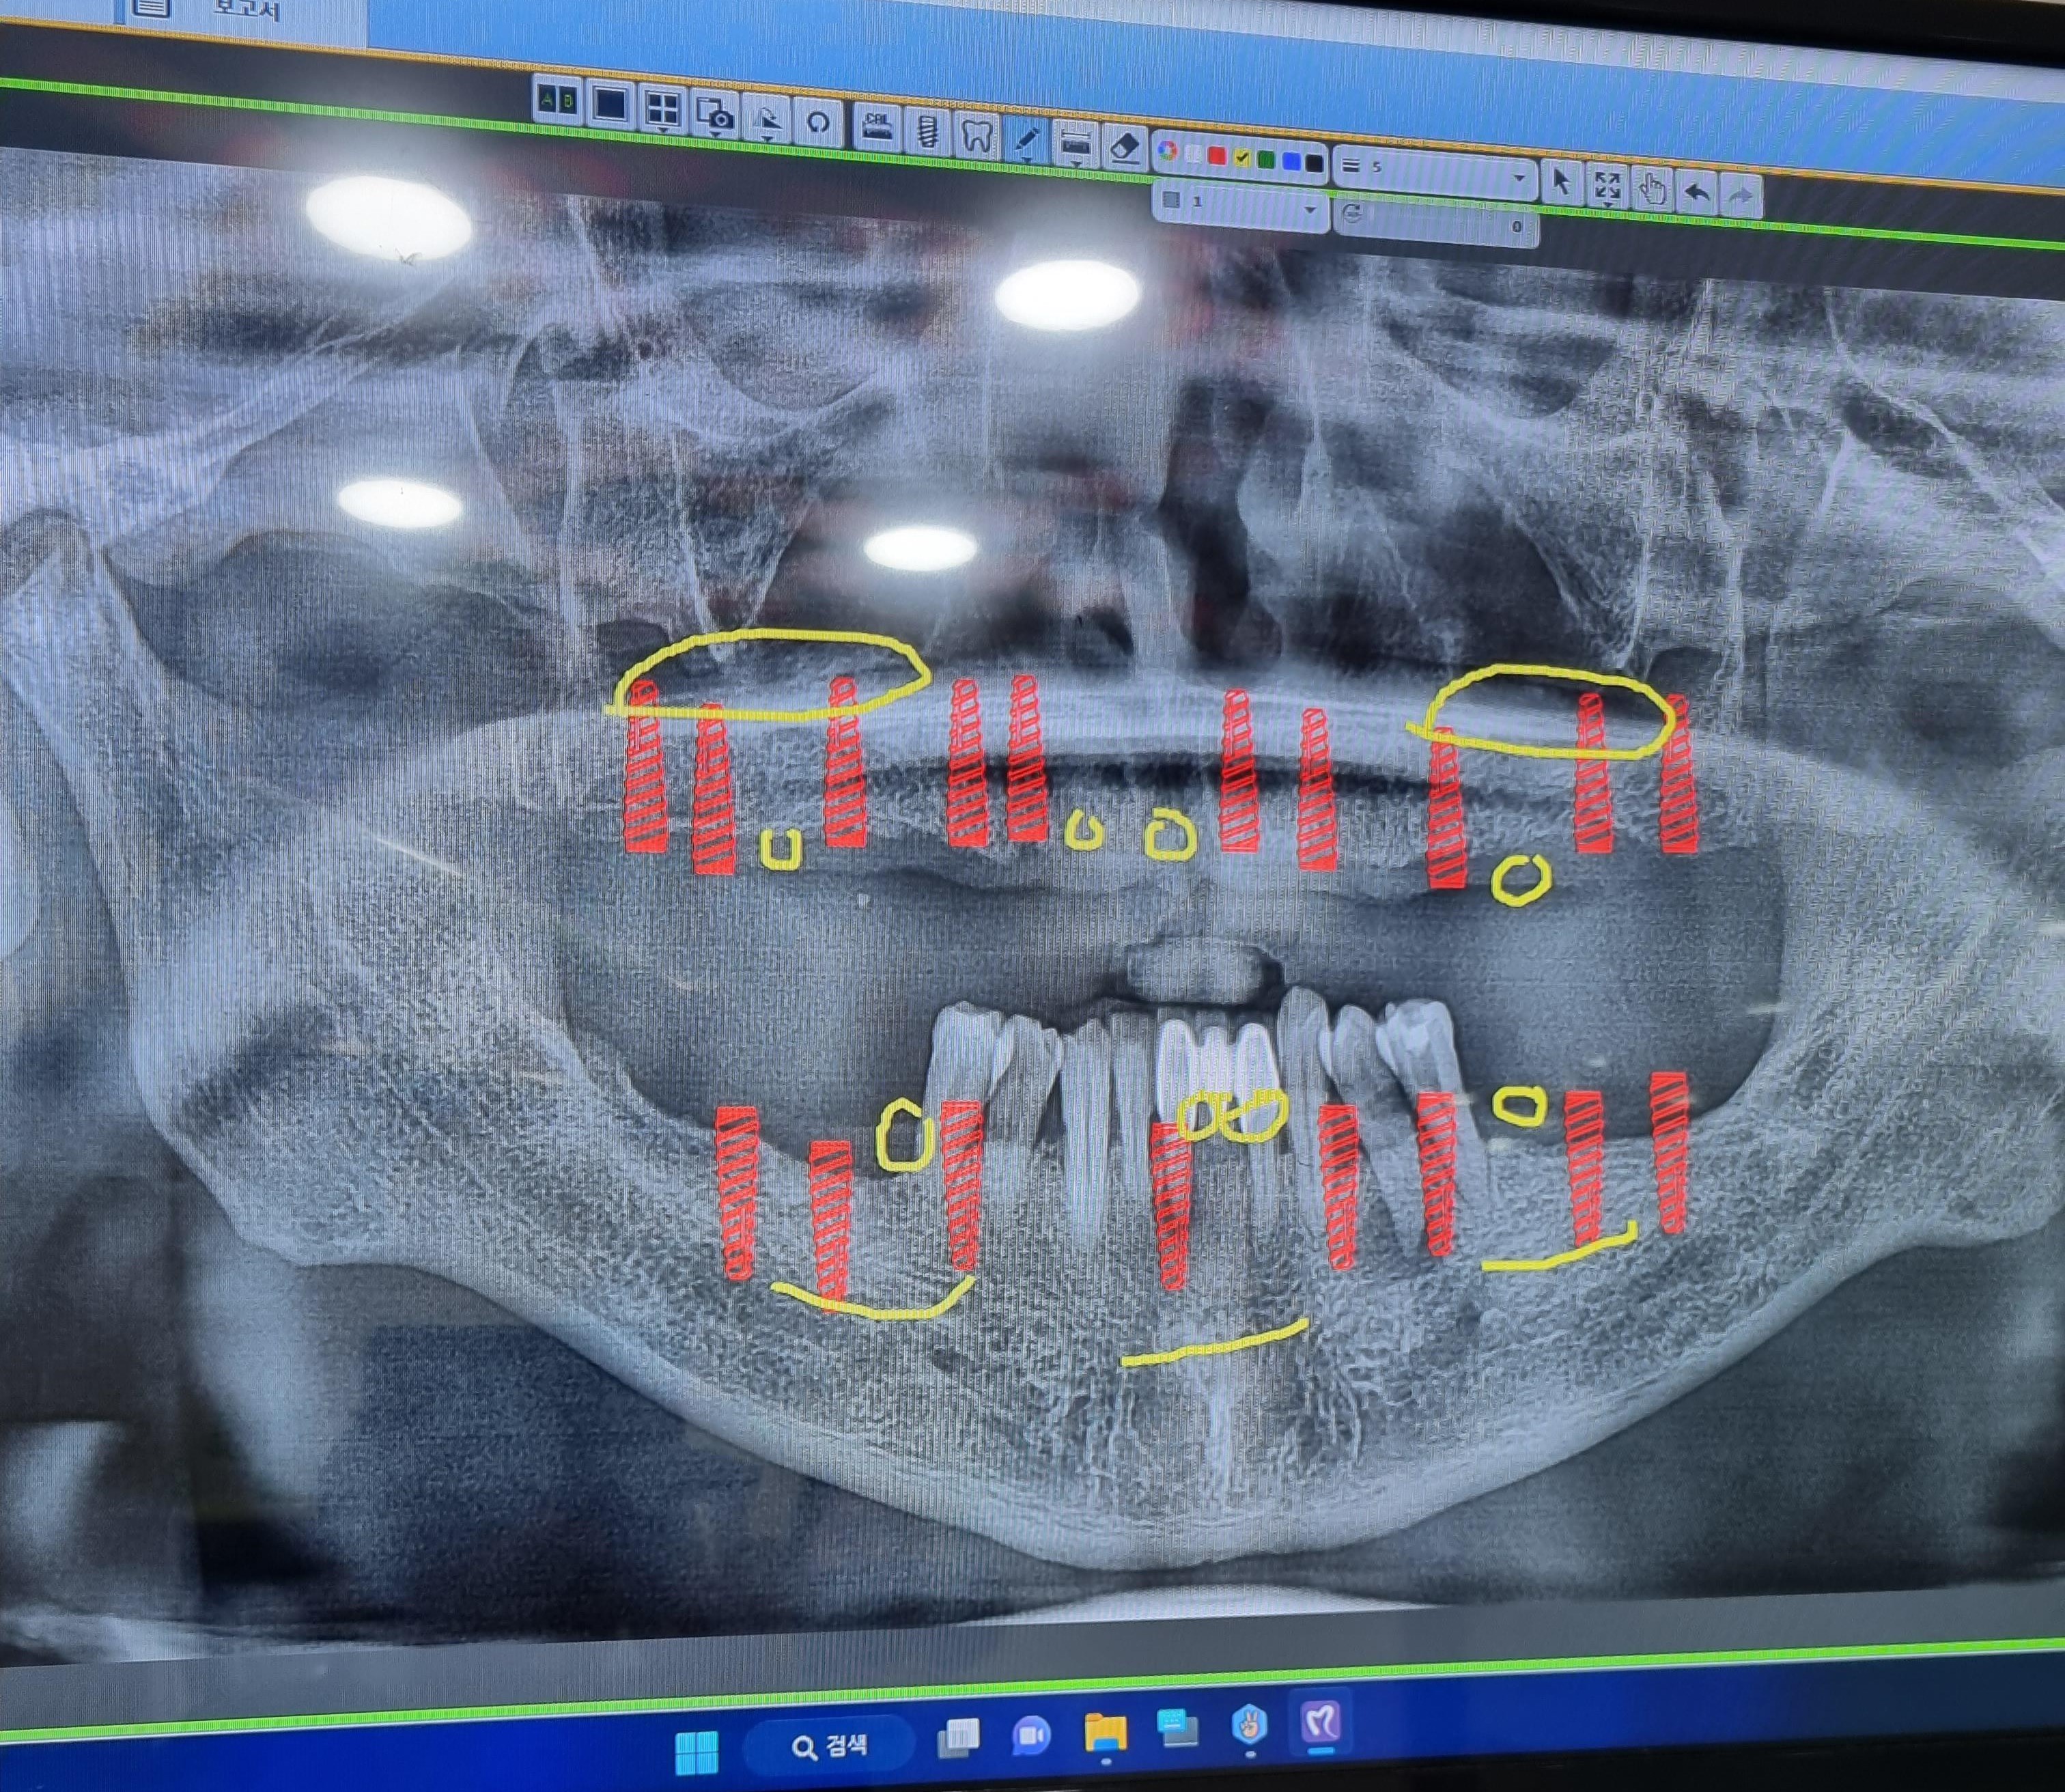

CT 촬영을 통해 구강口腔健康내  상태등을  검사하고  윗턱의  경우  모두  치아齒牙

치주염 齒周炎으로 인하여 결손된 상태라서 자연치아齒牙 2개와

전체  임플란트dental implant와  브릿지bridge를 같이  결합하여

전체  임플란트dental implant의 개수를  낮추는 방향으로  진행 하엿습니다.

임플란트dental implant를  윗니上顎 Over Denture 10   아랫니 下顎 치아齒牙 2 개를

제외하고 대부분의  치아齒牙  치주염 齒周炎 으로  좋지않은  상황이라

발치拔齒 뼈이식과  임플란트 8개를 식립植粒하기로 했습니다.

임플란트dental implant 18개을 식립植粒하는  수술이고.

1 上顎 Over Denture 76 X  32 X   X 23    4 X 67    10

下顎 765       1      XX 3   4 X 67      8